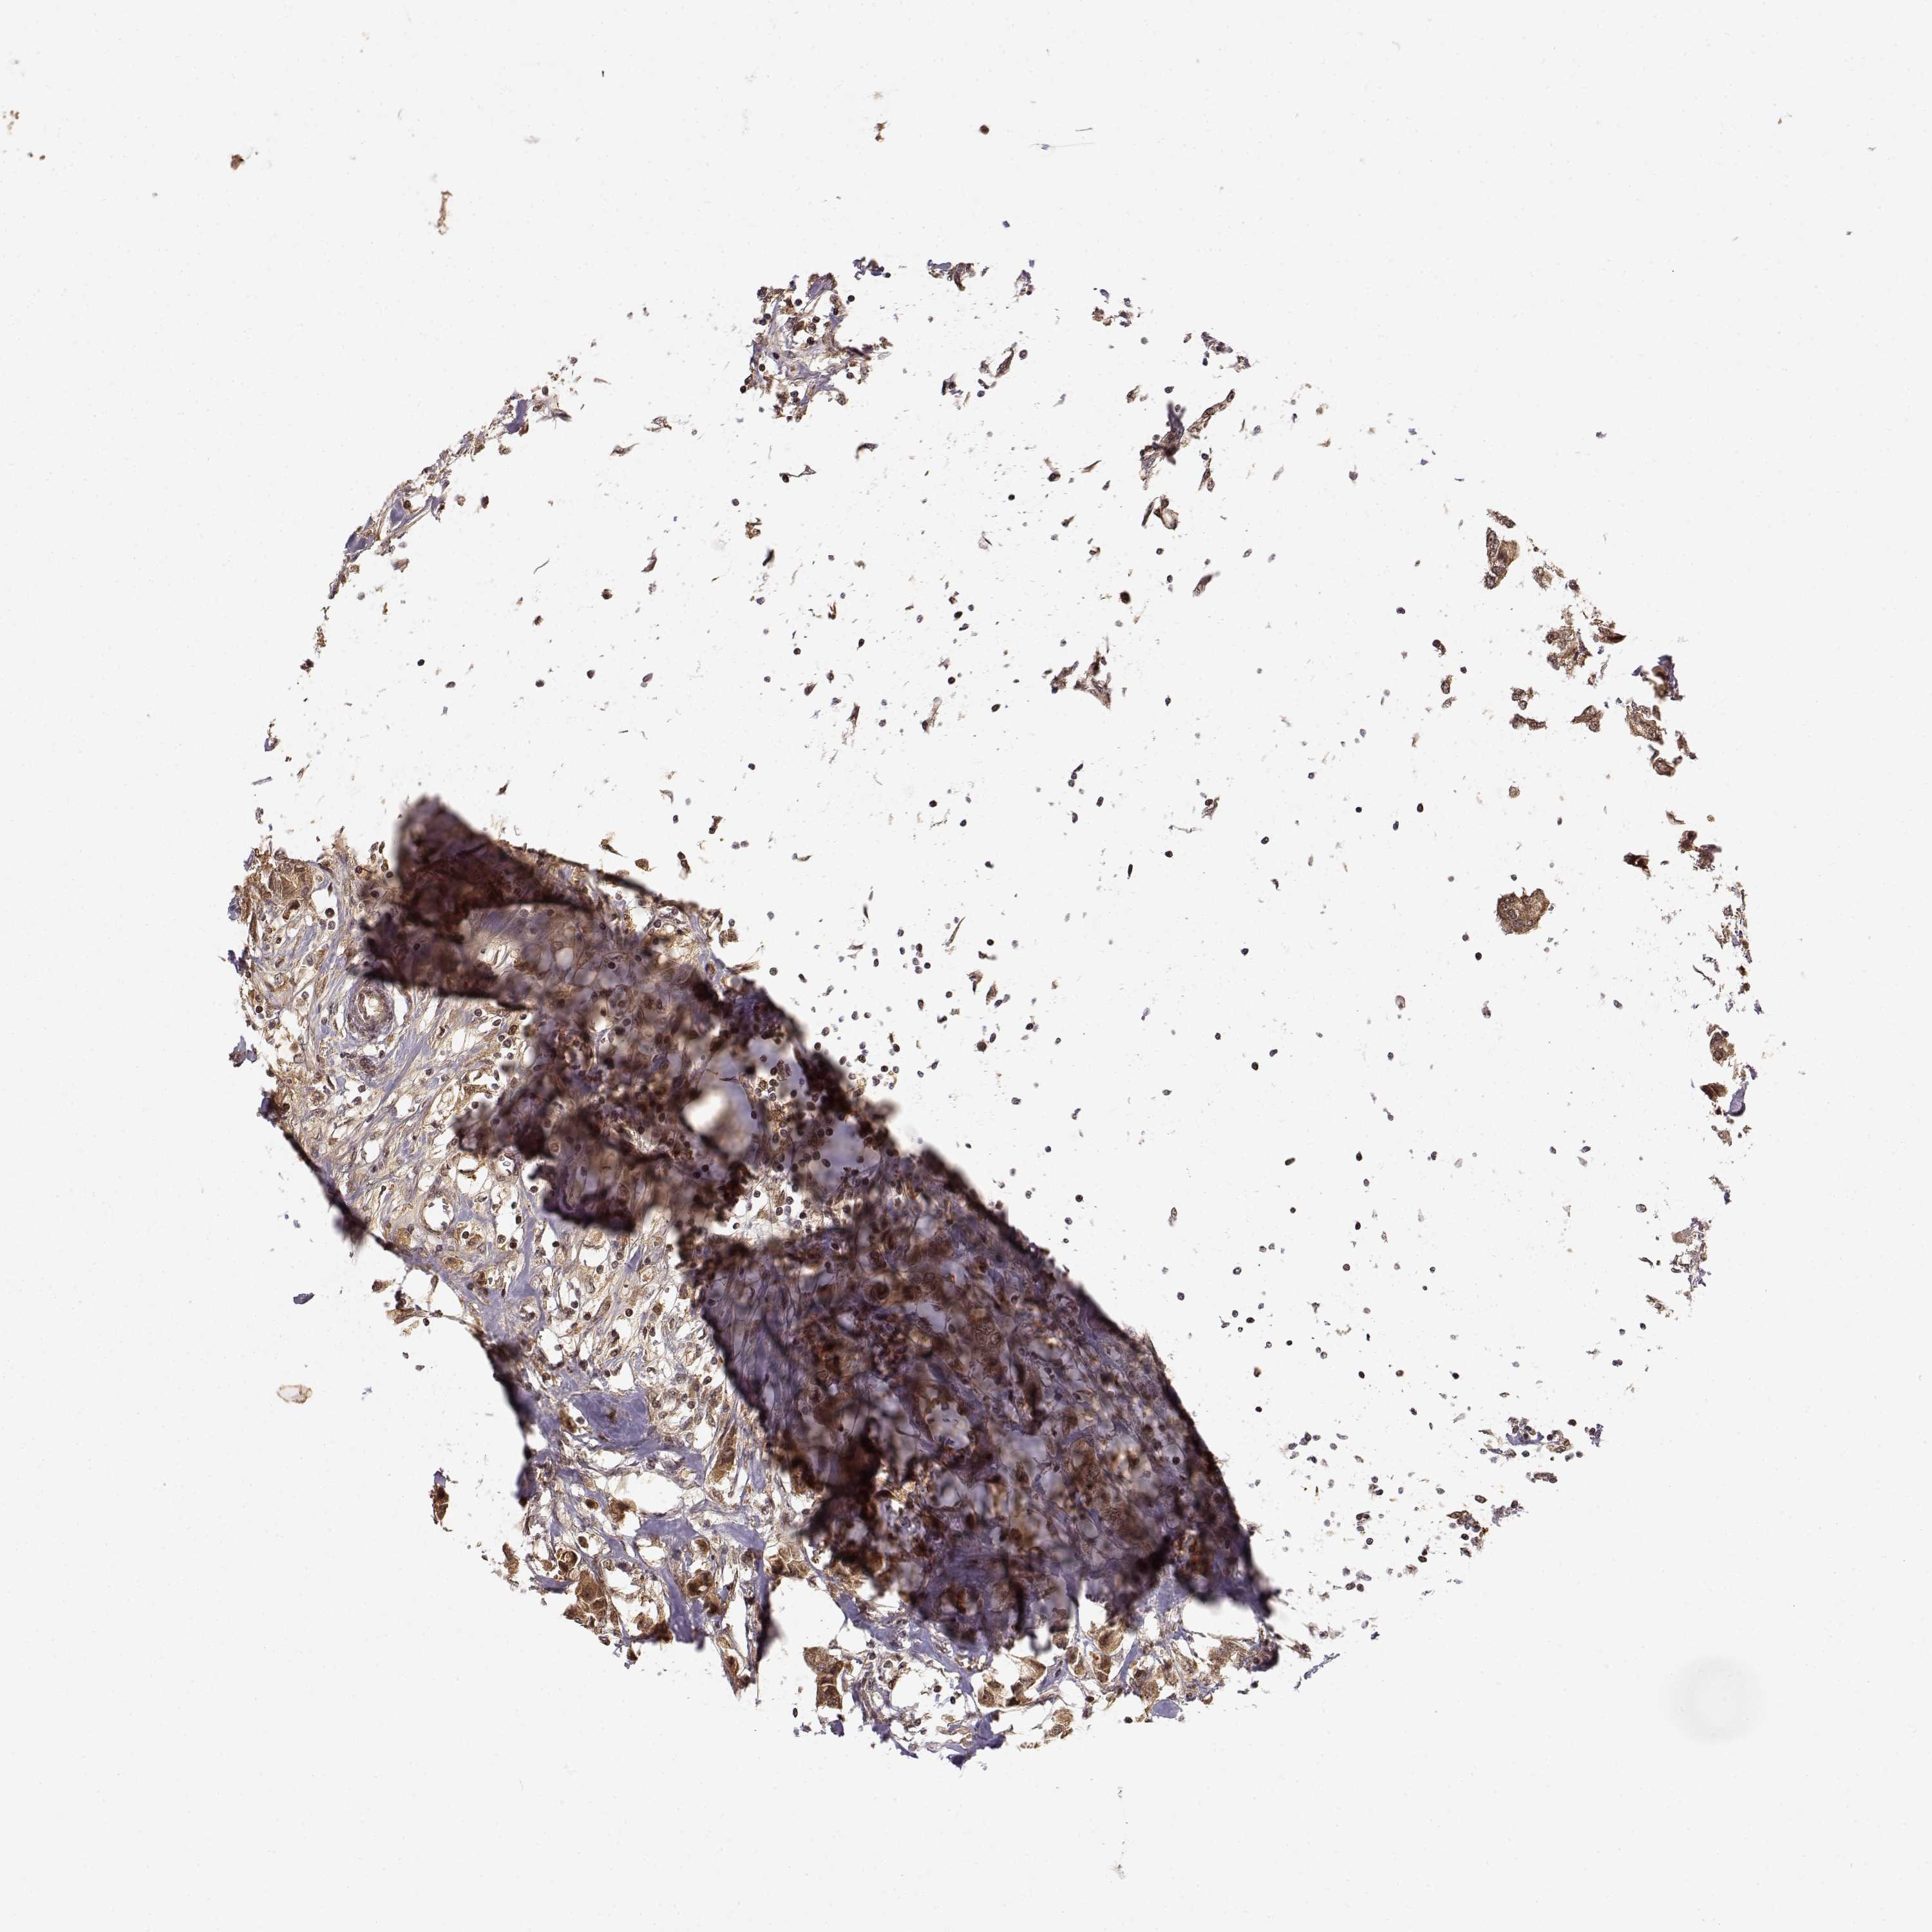

CANCER BREAST CANCER Show tissue menu

BRCA TCGA BRCA VALIDATION PROTEIN EXPRESSION